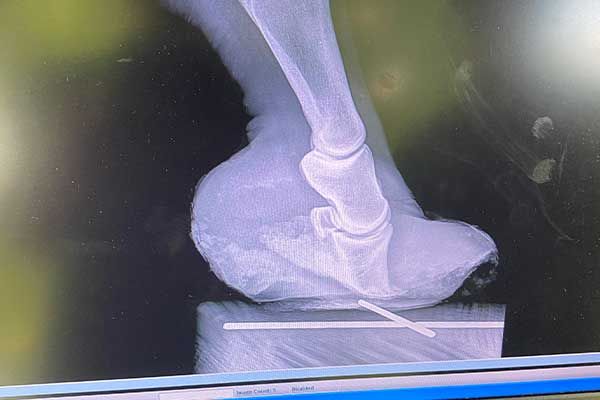

DIGITAL RADIOGRAPHY

We are proud to provide digital radiography services with our Sound-Eklin digital machine which produces superior images.

Radiographs are an important tool that can help us make a correct diagnosis for your pet. Our digital radiology service is staffed by caring, skilled professionals who will provide state-of-the-art care.